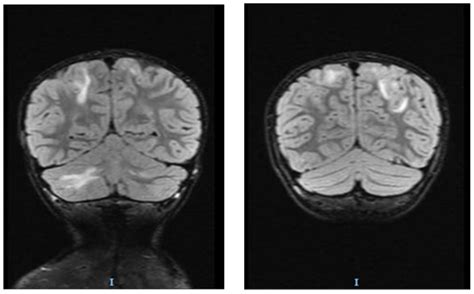

• Imaging Studies: CT scans or MRI to visualize the brain and detect any abnormalities.